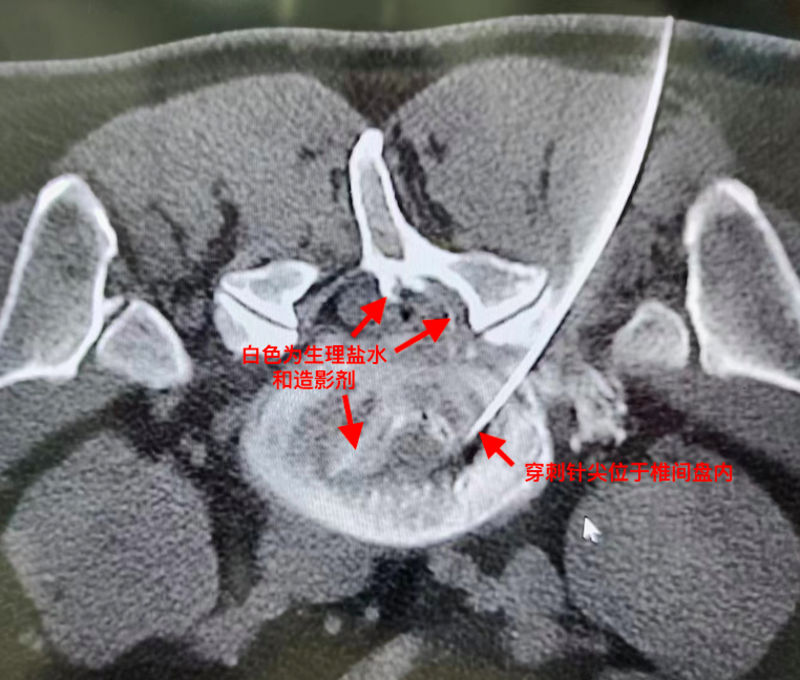

二周后再次住院二天,做了一次PRP后出院(见图2)

根据该患者严重的病情和巨大椎间盘脱出游离,如果仅仅采取椎管内消炎治疗(童氏精准无创介入治疗,)保守估计康复需要3个月(见图2)通过CT引导把PRP(富血小板血浆)直接注射到无血供组织的椎间盘内,给退变椎间盘撕裂口提供生长因子,创造修复条件,让退变椎间盘纤维环内中外三层组织结构均可以得到修复,这样不仅大大缩短了撕裂口修复的时间,同时也增强了椎间盘纤维环的坚固度。

穿刺针插入椎间盘内,注射生理盐水+造影剂,然后注射PRP(自体富血小板血浆)